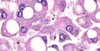

6 types of necrosis with mechanisms and examples of each

- Coagulative Necrosis: remains FIRM. ischemic infarction of any organ EXCEPT BRAIN. wedged shaped. Seen 1-3 days post MI

- Liquefactive Nectrosis: Brain (via microglial cells), Abscess (enzymes of neutrophils), Pancreatitis (enzymes of pancreas autodigest)

- Gangrenous necrosis: coagulative necrosis that resembles mummified tissue. ischemia of lower limb and GI

- Caseous necrosis: soft and friable, combo of liquefactive and coagulative. Seen in TB/Fungal where granulomas form

- Fat necrosis: chalky white due to Ca deposition. Trauma of fat –> saponification

- Fibrinoid Necrosis: damage to blood vessel wall. Bright pink staining (fibrin). Malignant hypertension and vasculitis